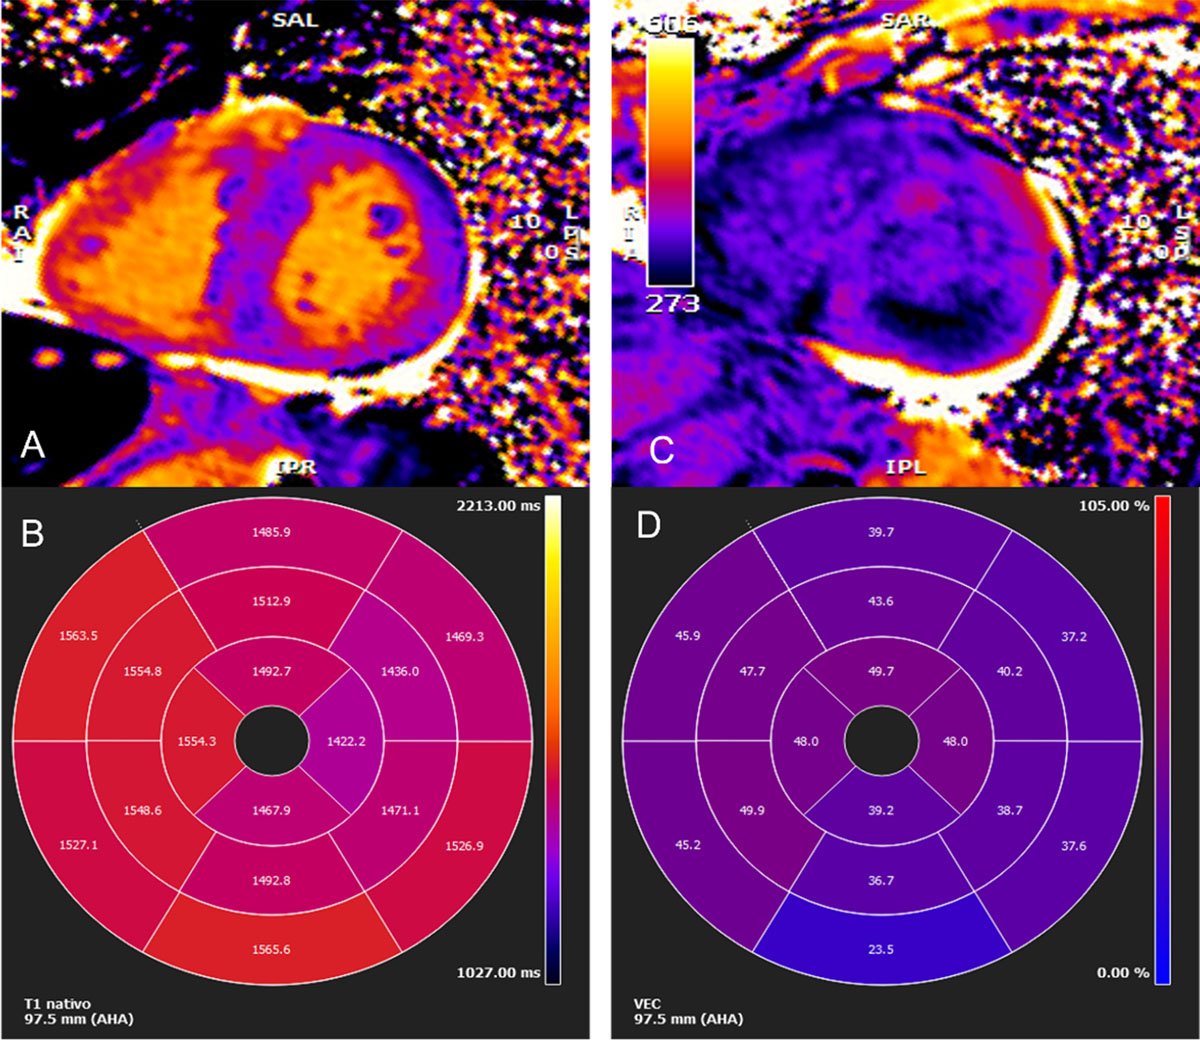

Figure 4

Cardiac magnetic resonance imaging. (A) Myocardial native T1 mapping (short axis) (B) Native T1 global polar map with abnormally increased T1 relaxation time (myocardial T1 values: 1,512±72 ms) (C) Post-contrast T1 (D) Global extracellular volume map, calculated from both native and post-contrast T1 myocardial values: in this case high above normal: 44±9%. (Images courtesy of Lusíadas Hospital, Lisboa, Portugal).